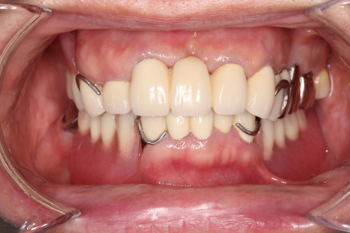

症例紹介

70代男性。修理を繰り返した義歯で噛みにくくなったために金属床義歯治療を行った症例。

-

治療前 -

治療後

治療内容:義歯の人工歯が摩耗していたうえに見た目にも支障があったため、噛み合わせの高さを挙上し、旧義歯に代わって、上下顎金属床義歯を製作しました。

治療期間:約12か月間

リスク・副作用:経年的な顎骨の吸収に対する調整の必要性、義歯を装着している違和感など